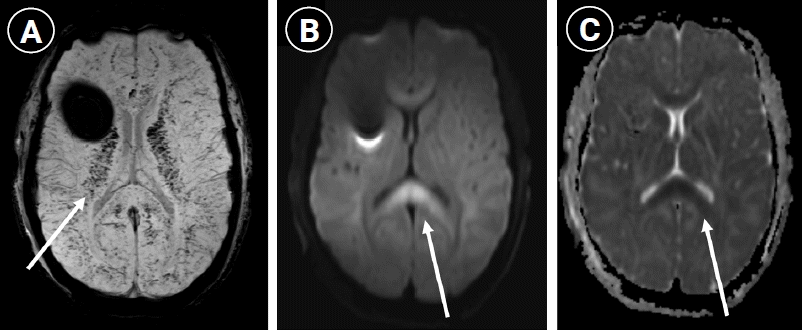

On day 7, cerebral MRI demonstrated ischemic lesions involving the corpus callosum, subcortical white matter to a lesser extent, and the cerebral cortex, together with multiple petechial hemorrhages and persistent cerebral edema previously noted on CT (Fig. 4). Biochemically, liver enzymes rapidly normalized, whereas kidney function worsened, requiring 14 days of continuous renal replacement therapy, followed by a single session of intermittent hemodialysis before full recovery. All microbiological investigations, including broad-range polymerase chain reaction and serological tests yielded negative results. The patient developed mild anemia and thrombocytopenia, necessitating occasional transfusions. Imaging also indicated pulmonary and renal infarcts, likely attributable to the sequestration of parasitized erythrocytes.

Fig. 4.

Magnetic resonance imaging findings. (A) T2-weighted images show multiple petechial hemorrhagic lesions typical of malaria, without hematoma. (B) Diffusion-weighted imaging and (C) apparent diffusion coefficient maps show ischemic involvement of the corpus callosum, with lesser involvement of the subcortical white matter, and diffuse involvement of the cerebral cortex. Arrows in each panel highlight the regions of pathological involvement described in the text.